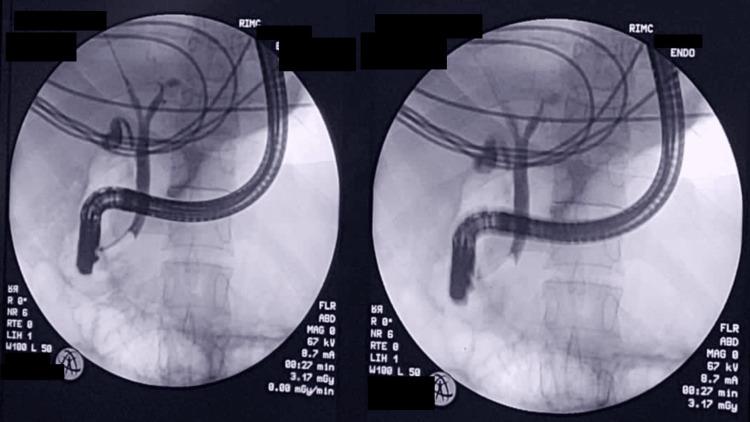

A contracted or "vanishing" gallbladder is a condition characterized by severe atrophy or fibrosis of the gallbladder, often resulting from chronic inflammation, recurrent cholecystitis, gallstone disease, or metabolic disorders such as diabetes and chronic alcohol use. The etiopathogenesis involves progressive fibrosis due to persistent biliary obstruction, chronic infection, or impaired blood flow, particularly in patients with liver cirrhosis. While the exact incidence remains unclear, it is more prevalent in individuals with long-standing hepatobiliary diseases or metabolic syndromes. Common symptoms include severe right upper quadrant pain, jaundice, nausea, vomiting, and signs of obstructive jaundice, such as dark urine and pale stools. Diagnostic investigations typically involve ultrasound, contrast-enhanced computed tomography (CECT), magnetic resonance cholangiopancreatography (MRCP), and endoscopic retrograde cholangiopancreatography (ERCP) to assess biliary obstruction, liver pathology, and gallbladder morphology. Treatment requires a multidisciplinary approach, including initial ERCP for biliary decompression, followed by surgical intervention (laparoscopic or open cholecystectomy), with conversion to open surgery often necessary due to dense adhesions and fibrosis. Postoperative care focuses on managing comorbidities, preventing complications, and long-term monitoring of liver health. This case report presents the challenging management of a 34-year-old male with a history of diabetes mellitus, chronic alcohol use, and liver cirrhosis, who presented with severe right upper quadrant pain, jaundice, and ascites. Initial evaluation revealed cholangitis, calculous cholecystitis with choledocholithiasis, and imaging findings consistent with liver cirrhosis. The patient underwent ERCP for biliary stenting and sludge extraction, followed by an attempted laparoscopic cholecystectomy. Intraoperatively, dense adhesions and fibrosis obscured the gallbladder, confirming a contracted or "vanishing" gallbladder, prompting conversion to an open procedure. The case highlights the diagnostic complexities of contracted gallbladders, which often result from chronic inflammation, fibrosis, or metabolic disorders. Preoperative imaging, including ultrasound and MRCP, played a critical role in identifying biliary obstruction and liver pathology. However, intraoperative findings necessitated adaptive surgical decision-making to mitigate risks such as bile duct injury or hemorrhage. The patient's multiple comorbidities further complicated management, emphasizing the need for a multidisciplinary approach involving gastroenterologists, surgeons, and hepatologists. Postoperative recovery was closely monitored for complications, including infection and bile leaks. The patient was discharged with follow-up care focusing on liver health, diabetes management, and alcohol cessation. This report underscores the importance of thorough preoperative assessment, flexibility in surgical technique, and collaborative care in optimizing outcomes for patients with complex gallbladder pathology. Future research should explore long-term outcomes and improved imaging techniques to enhance surgical planning for such challenging cases.